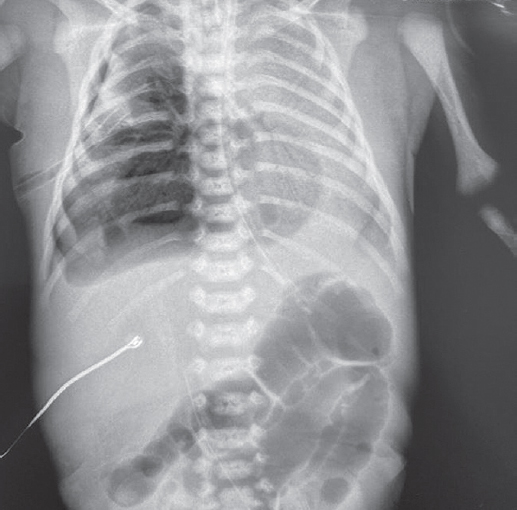

На этом фоне отмечается выраженный положительный эффект в виде увеличения SpO2 с 7–23 до 90 %, на контрольной рентгенограмме сразу после введения порактанта альфа (рис. 3) отмечается незначительное улучшение пневматизации левого легкого, сохраняется свободный воздух в правой плевральной полости.

Рис. 3. Рентгенограмма органов грудной клетки новорожденного после монобронхиального введения сурфактанта

Fig. 3. Chest X-ray of newborn after monobronchial surfactant administration

На контрольной рентгенограмме через 6 ч после манипуляции сохраняются признаки правостороннего пневмоторакса, отмечается неравномерное восстановление воздушности левого легкого. Снизить параметры ВЧО ИВЛ не представлялось возможным. В последующем отмечено прогрессирование явлений дыхательной недостаточности с десатурацией (SpO2 46 %), по анализу газового состава венозной крови отмечается выраженная венозная гипоксемия (рО2 13 мм рт. ст.), гиперлактатемия (6,7 ммоль/л). Сохраняется выраженная артериальная гипотензия, в связи с чем скорость введения адреналина увеличена до 0,2 мкг/(кг · мин), на этом фоне достигнута стабилизация.